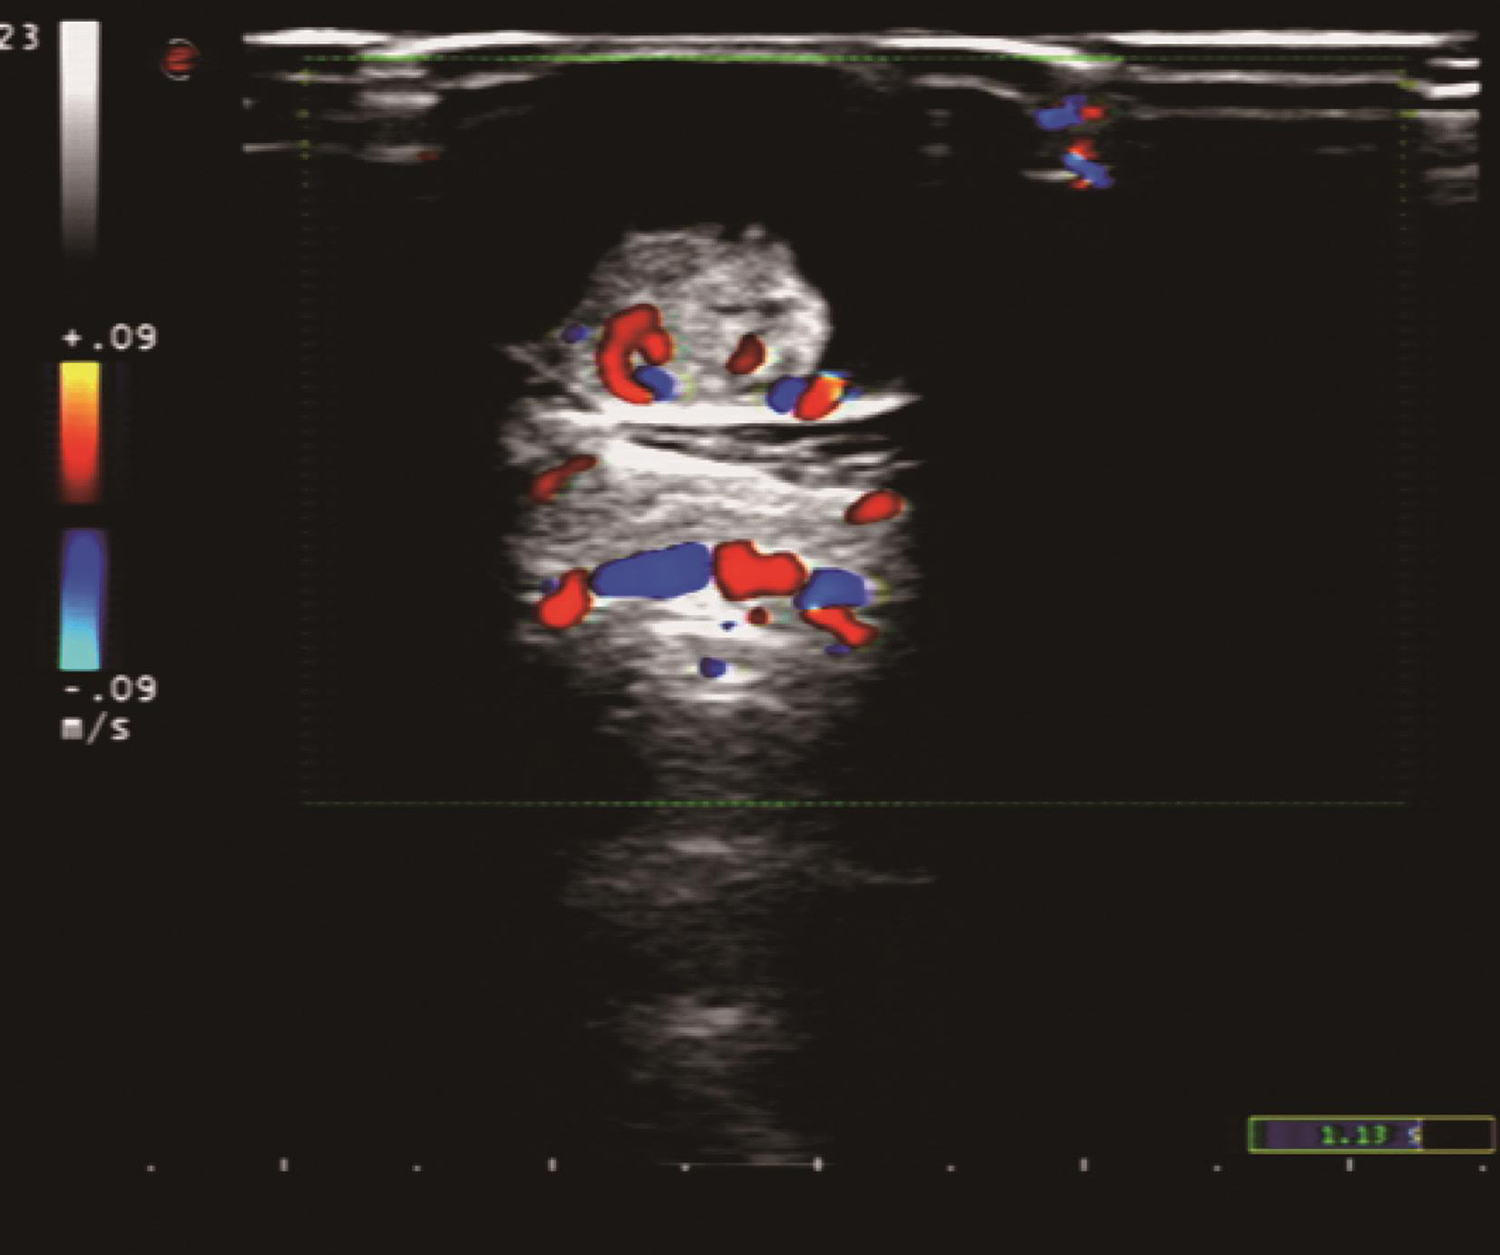

1.2017年8月8日颈部B超

甲状腺右叶可见一3.0cm×1.9cm×1.7cm大小的中低回声结节,边界尚清,内回声不均匀,其中心部可见一长约1.2cm的强回声;峡部可见一直径2.4cm大小的囊实性混合回声结节,边界清楚,回声不均匀,实质部分中等回声。CDFI可见较丰富血流信号(图1);左叶上极可见一直径0.5cm大小的低回声结节,边缘毛糙,其内可见点状强回声;右颈Ⅱ、Ⅲ、Ⅳ、Ⅵ区可见多个肿大淋巴结,最大者直径2.7cm,其内可见斑状及半弧形强回声(图2)。

图1 颈部超声示甲状腺右叶中低回声结节CDFI可见较丰富血流信号